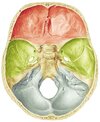

now, just for reference, this part of the skull is what we will be talking about in this thread.

9ee0459ab80d4f88579ea68bc6c14a07485e23b7.png

062077ad6465a7e241a5c28f3bbf7e4d4143aa33.jpg